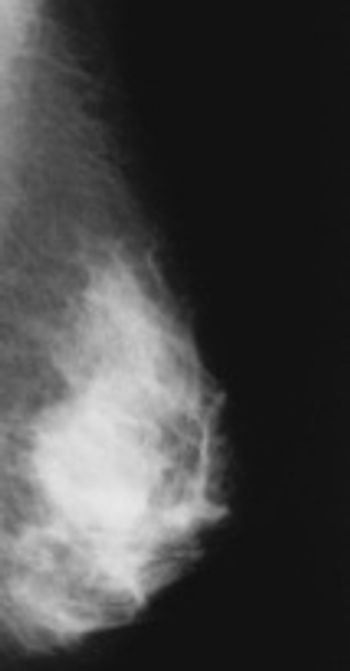

Mammography versus magnetic resonance imaging (MRI) has been a long-standing debate among industry leaders. The general consensus today, however, is while both tests effectively detect breast cancer and can work hand-in-hand, mammography is still indispensable.